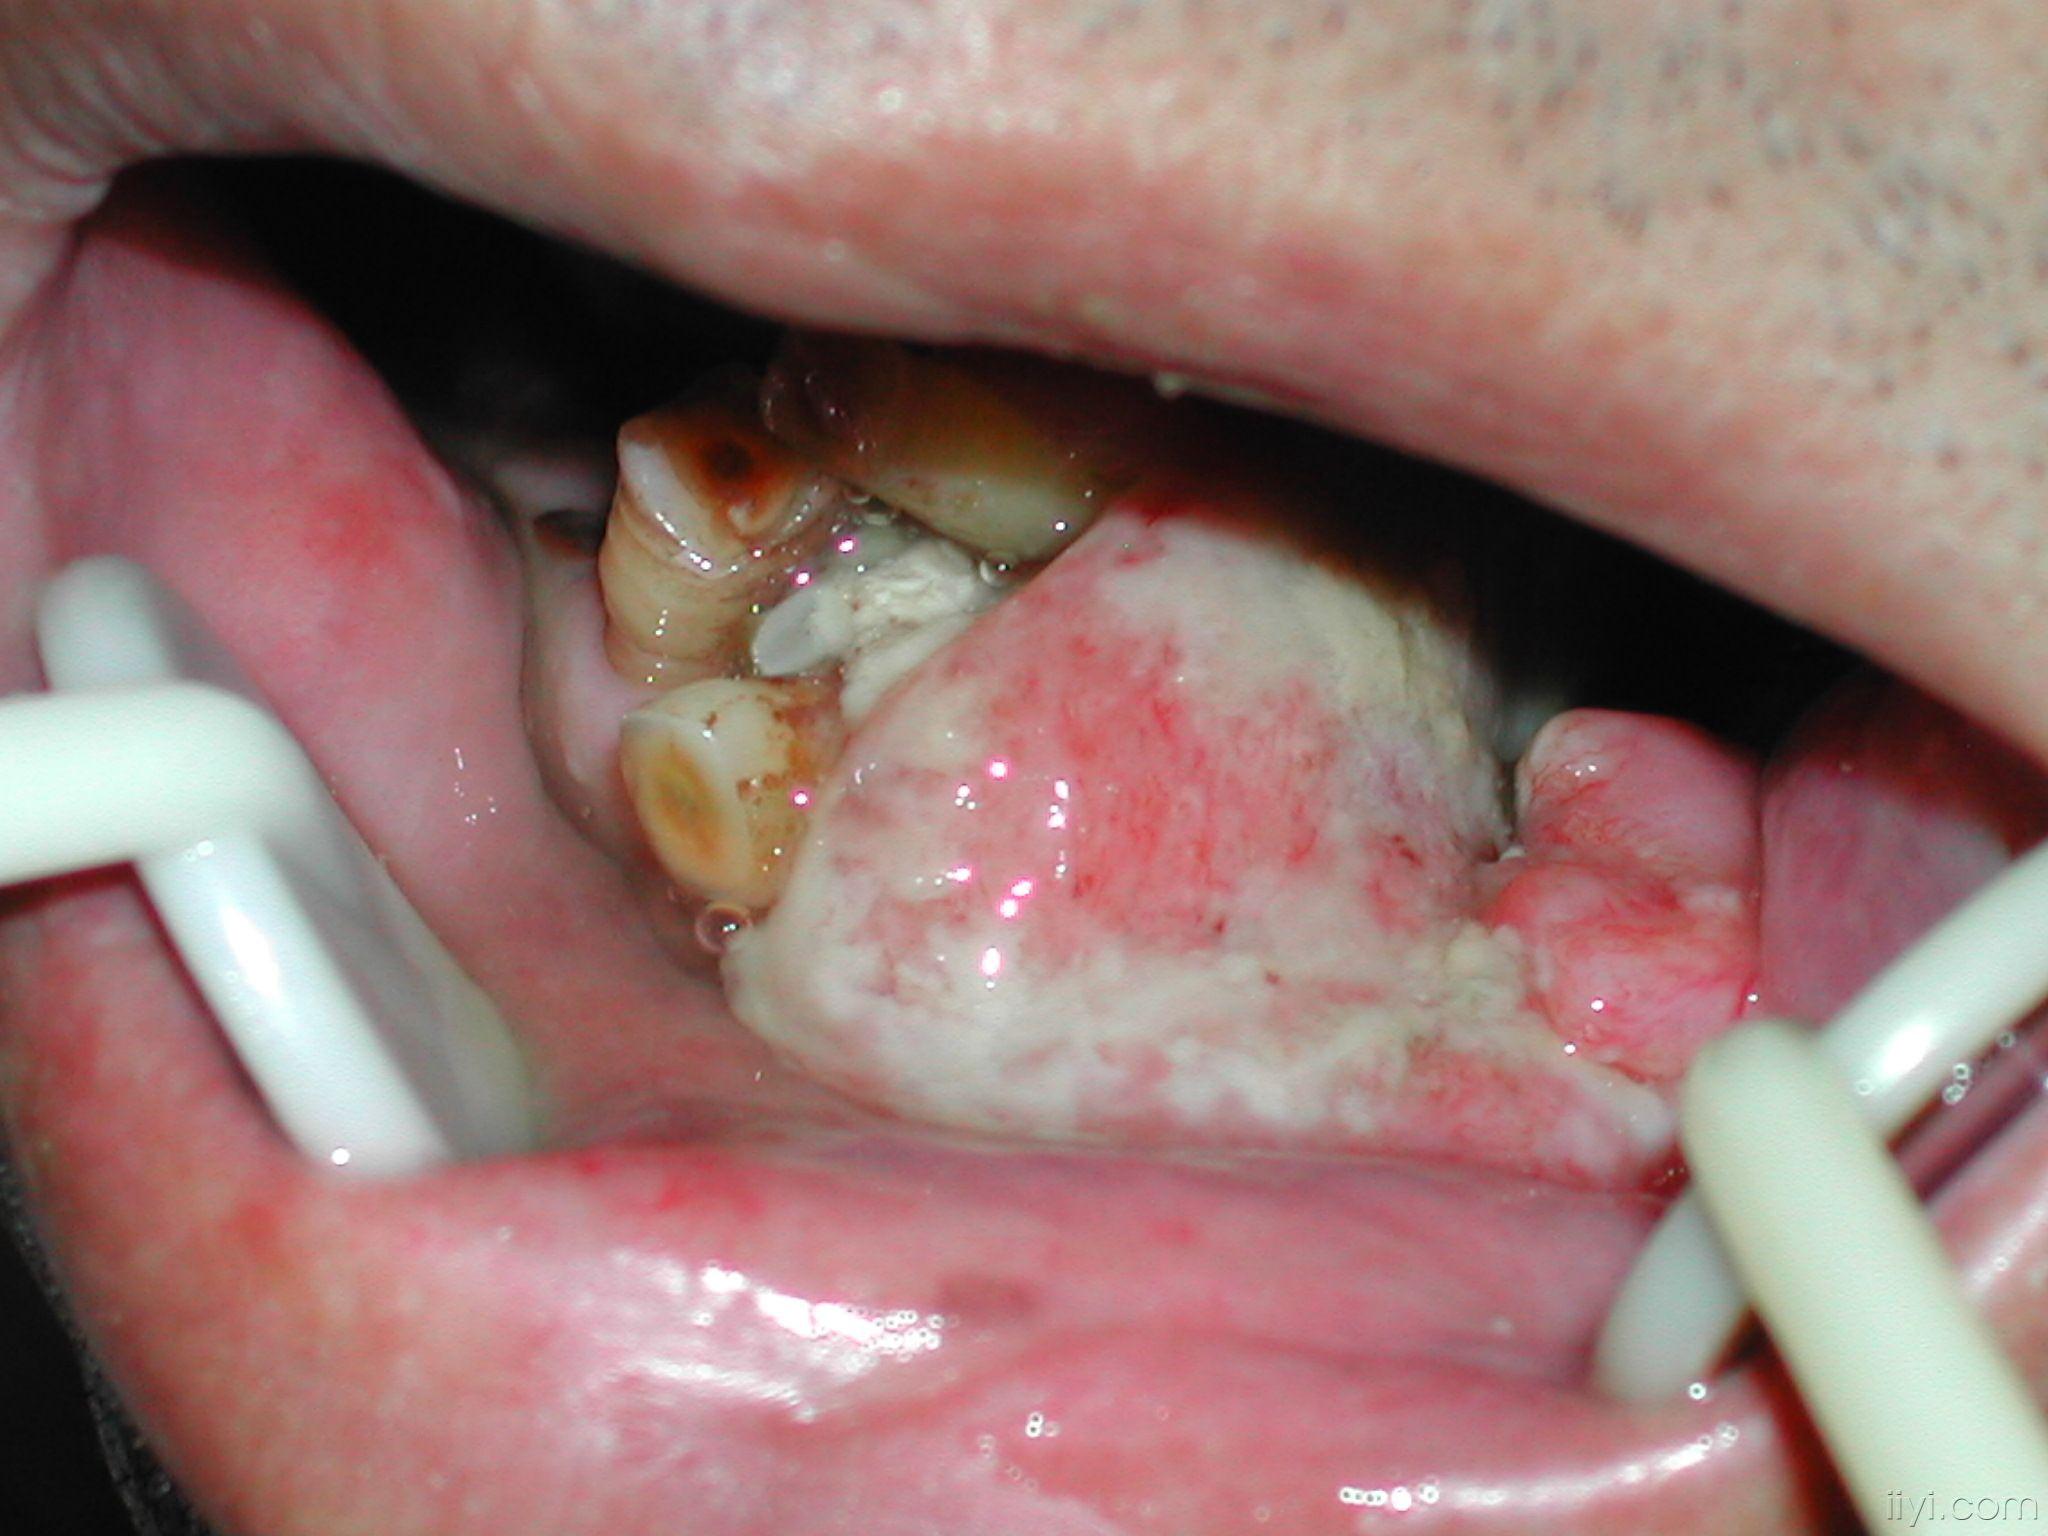

牙龈癌

牙龈癌1例

【图】牙龈癌的早期症状图片展示 4种临床表现你了解吗?